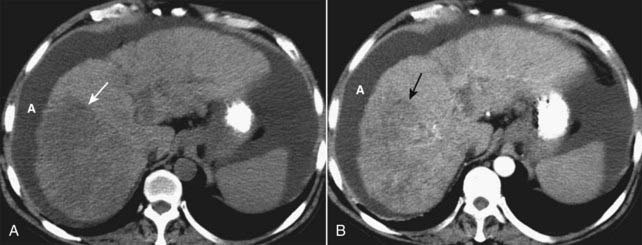

image MRI is the most accurate modality in the evaluation of a fatty liver, using a phenomenon called chemical shift imaging to detect the presence of microscopic, intracellular lipid present in such a liver. Chemical shift relates to the way that lipid and water protons behave in the magnetic field (Fig. 18-28).

image

Figure 18-28 Fatty liver, MRI.

Using a phenomenon called chemical shift imaging to detect the presence of microscopic, intracellular lipid present in a fatty liver, MRI is the most accurate imaging modality in identifying a fatty liver. Chemical shift relates to the way that lipid and water protons behave in the magnetic field. A, The liver (solid white arrow) appears normal, brighter than the spleen (S). B, This is called an opposed-phase image, and it demonstrates marked signal loss (signal dropout) throughout the liver (dotted white arrow), indicating a fatty liver. Most of the liver is now darker than the spleen (S), except for the caudate lobe (C), which is normal.